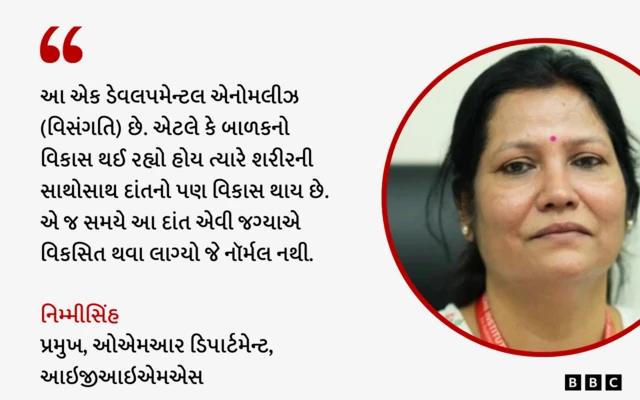

આ સવાલના જવાબમાં હૉસ્પિટલના ઓએમઆર ડિપાર્ટમેન્ટનાં હેડ નિમ્મીસિંહ જણાવે છે કે, "આ એક ડેવલપમેન્ટલ એનોમલીઝ (વિસંગતિ) છે. એટલે કે જ્યારે બાળકનો વિકાસ થઈ રહ્યો હોય છે ત્યારે તેના શરીરની સાથોસાથ દાંતનો પર વિકાસ થઈ રહ્યો હોય છે. એ જ સમયે આ દાંત ખોટી જગ્યાએ વિકસિત થવા લાગે છે."